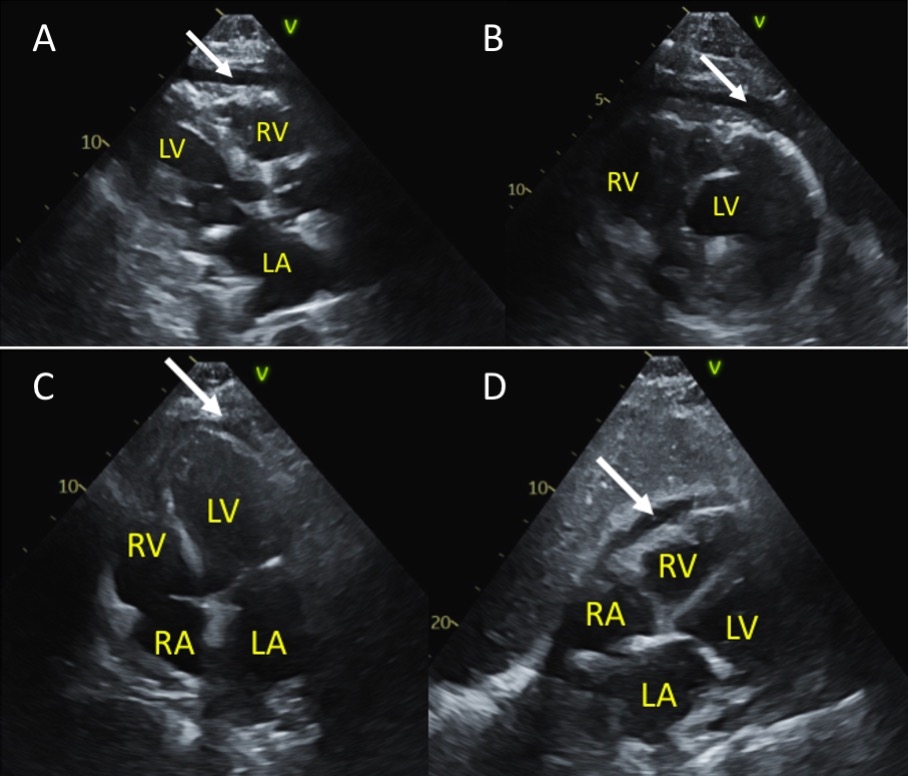

This case illustrates a rare progression from cardiorenal syndrome and uremic pericarditis leading to cardiac tamponade (Fig.1). Despite a small pericardial effusion and lack of classic echocardiographic signs (Fig.2), rapid fluid accumulation likely resulted in tamponade physiology, supported by hemodynamic and clinical findings. Based on ESC guidelines, typical management involves HD. However, successful use of anti-inflammatory treatment in place of dialysis was utilized due to contraindications. Upon readmission, the absence of tamponade signs suggested a slower effusion progression, reinforcing the initial diagnosis of rapid-onset tamponade in a vulnerable myocardium.